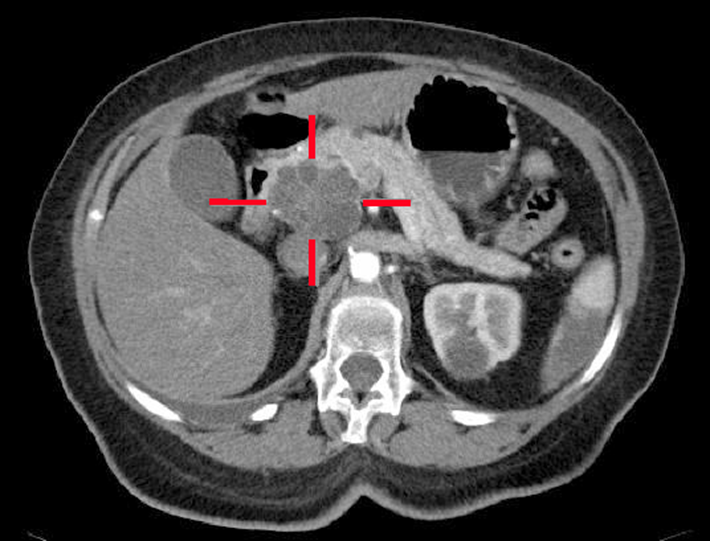

Pancreatic Pseudocyst

is defined as fluid-filled cavity.

They occur due to inflammation, necrosis, or hemorrhage.

Causes:

Acute pancreatitis

Trauma